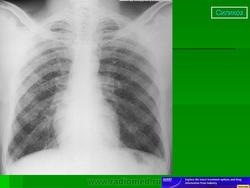

Силикоз - наиболее распространенная и тяжело протекающая форма П. Особенно неблагоприятное течение отмечается при воздействии пыли с большим содержанием свободного диоксида кремния (у пескоструйщиков, обрубщиков, бурильщиков, проходчиков, размольщиков кварца и др.). В этих условиях силикоз может развиться при непродолжительном рабочем стаже (менее 10 лет), более выражена склонность к прогрессированию пневмофиброза и после прекращения контакта с пылью, чаще наблюдаются осложнения и развивается туберкулез. Рентгенологически в большинстве случаев выявляются узелковая и узловая формы процесса. При воздействии пыли с малым содержанием свободного диоксида кремния (менее 10%) чаще встречаются интерстициальная и мелкоузелковая формы силикоза, которые прогрессируют реже и медленнее. Силикоз отличается неблагоприятным течением у лиц, начавших работать в очень молодом и среднем (после 40 лет) возрасте.

При рентгенологическом исследовании различают три формы П.: интерстициальную, узелковую и узловую (или конгломеративную), в развитии которых наблюдается определенная стадийность. Узелковые формы П. встречаются чаще всего при силикозе, антракозе и антракосиликозе, при некоторых металлокониозах (сидерозе, баритозе, манганокониозе, бериллиозе, сидеросиликозе). При П., вызываемых вдыханием пыли, не содержащей свободной двуокиси кремния, преобладают интерстициальные формы.

При узелковом П. даже в начальных стадиях болезни изменения в легких более специфичны и их связь с профвредностью устанавливается более уверенно. В I стадии на фоне усиленного легочного рисунка обнаруживается множество узелковых образований диаметром 1-3 мм, большая часть которых концентрируется в прикорневых отделах легких. Форма узелков округлая, очертания четкие. Тени корней легких умеренно расширены, тяжисты.